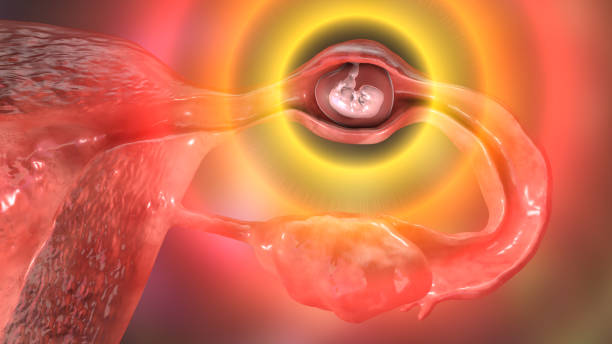

골반 통증 원인 6. 자궁내막증, 자궁근종

골반 통증 원인 일곱 번째는 자궁내막증 혹은 자궁근종입니다. 여성은 임신과 출산을 위해서 남성 골반과는 구조적으로 다른데 남성 골반보다 넓고 짧아 골반 내 공간이 더 넓은 특징을 가지고 있어 골반 통증에 더욱 취약합니다.

자궁내막증의 경우 생리 혹은 생리 직전에 골반통을 유발하는데 이는 자궁내막조직과 자궁이 아닌 다른 부위의 조직에 부착하여 증식하면서 발생합니다. 자궁근종의 경우 자궁의 평활근에 생기는 종양의 일종으로 별다른 증상이 없을 수 있지만 근종의 위치나 크기에 따라 다양한 증상이 유발되며 이로 인하여 각종 골반통, 생리통, 골반 압박감과 생리량 과다 증상 등이 발생할 수 있습니다.